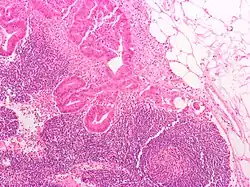

Lâmina histológica de um adenoma tubular, um tipo de pólipo colonial, e um precursor do cancro colorretal.

Adenocarcinoma invasivo (o tipo mais comum de cancro colorretal). Células cancerosas estão no centro e à esquerda inferior da imagem (em azul).

O tipo do tumor é geralmente diagnosticado através da análise de tecido removido através de uma biópsia ou cirurgia. O diagnóstico patológico geralmente contém a descrição histológica do cancro, e o grau. O tipo mais comum de cancro colorretal é adenocarcinoma, que compõe 95% dos casos - acredita-se que a maioria dos casos de cancro colorretal envolvam tumores originários de pólipos adematosos. Outros tipos, mais raros, de cancro colorretal, incluem linfoma e carcinoma espinocelular. As causas do cancro colorretal não são conhecidas com exatidão no presente.

Adenocarcinoma é um tipo de tumor maligno epitelial, que se origina do epitélio glandular da mucosa colorretal. Tal tumor invade a parede, infiltrando a mucosa muscular, a submucosa, e daí, a muscularis propria. As células do tumor abrigam estruturas tubulares irregulares, de estrutura pluristratificada, lúmens múltiplos, e estromas reduzidos. Por vezes, as células do tumor secretam muco, que invade o fluido intersticial, produzindo grandes agrupamentos de muco e colóide (que, visualmente, aparecem como "espaços vazios") - é o chamado adenocarcinoma colóide, pouco diferenciado. Se o muco permanece dentro da célula do tumor, o muco empurra o núcleo celular para a periferia da célula - célula do tipo signet-ring. Dependendo da arquitetura glaudular, pleomorfismo celular, e padrão da secreção de muco, o adenocarcinoma pode ser categorizado em três graus de diferenciação: bem diferenciado, moderadamente diferenciado, e mal diferenciado.[48]